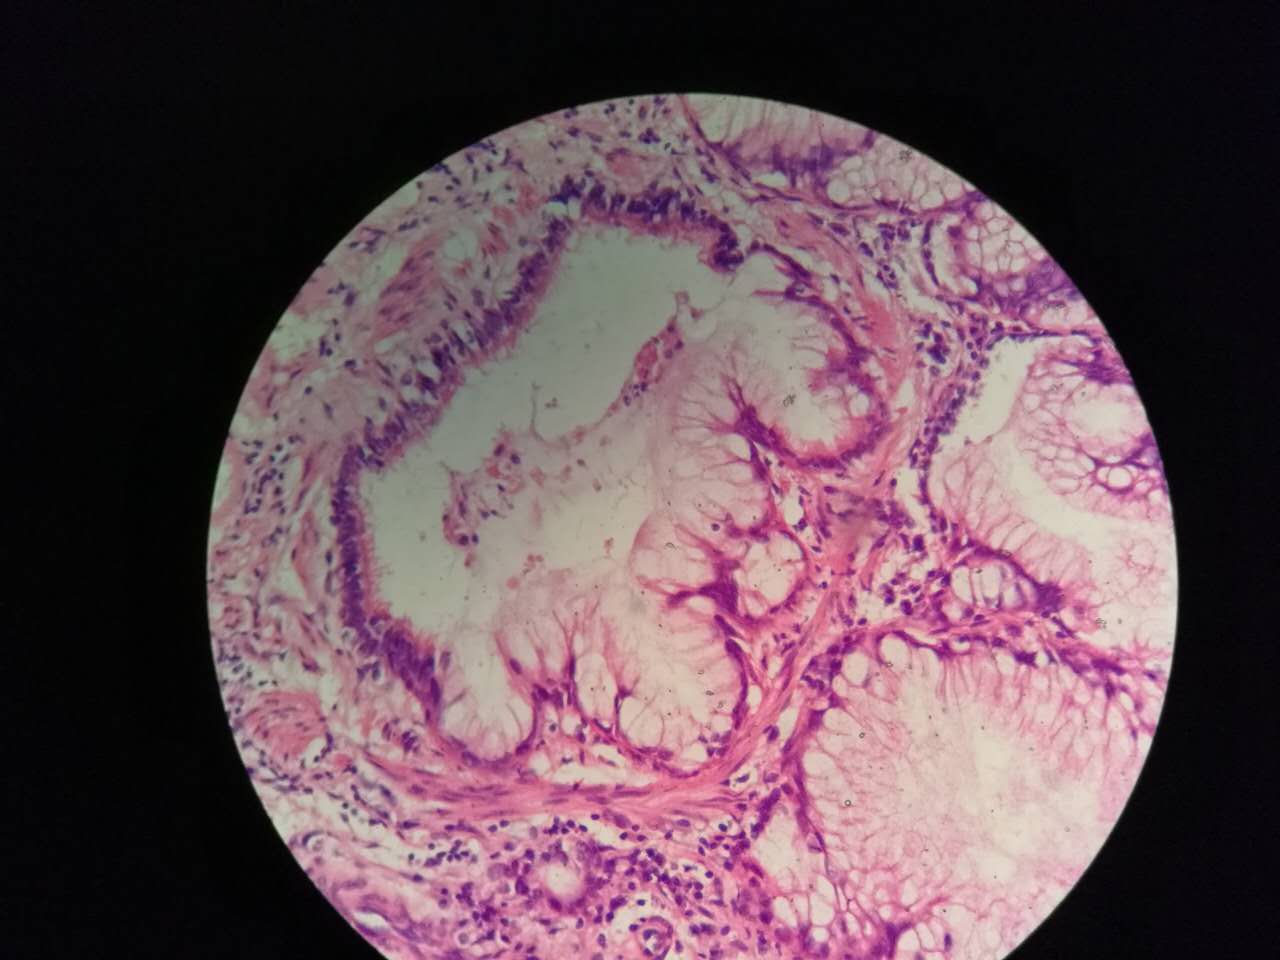

这个生长密集,相对要重

这个细支气管,一半癌浸润

肿瘤细胞形态仍然相似

中央有个肺血管,说明破坏力不强

也会有些坏死,连同粘液咳出去,就形成实变区内的空洞